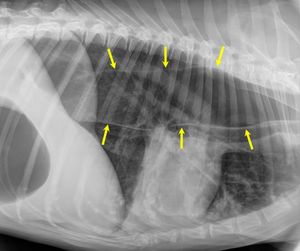

거대식도증에 걸린 개의 흉부 X-레이 사진. 식도의 가장자리는 노란색 화살표로 표시되어 있다. (이 이미지에서 개의 머리 쪽은 오른쪽이고 꼬리 쪽은 왼쪽이다.)